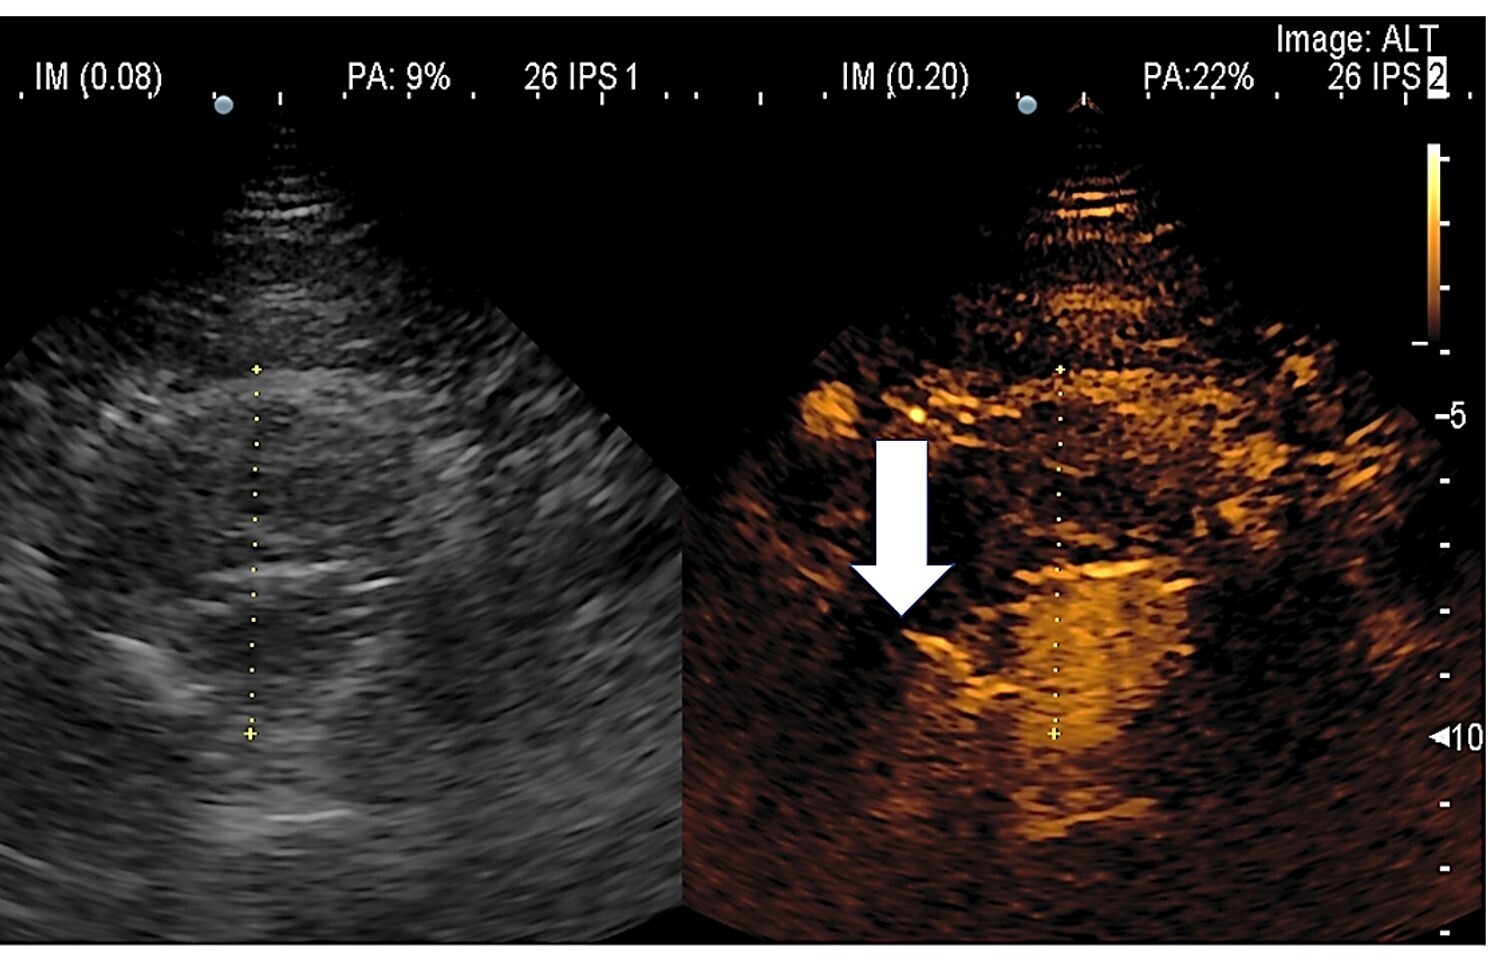

* La mise en évidence d'une endofuite est très optimisée par un examen écho Doppler avec un agent de contraste – SONOVUE.